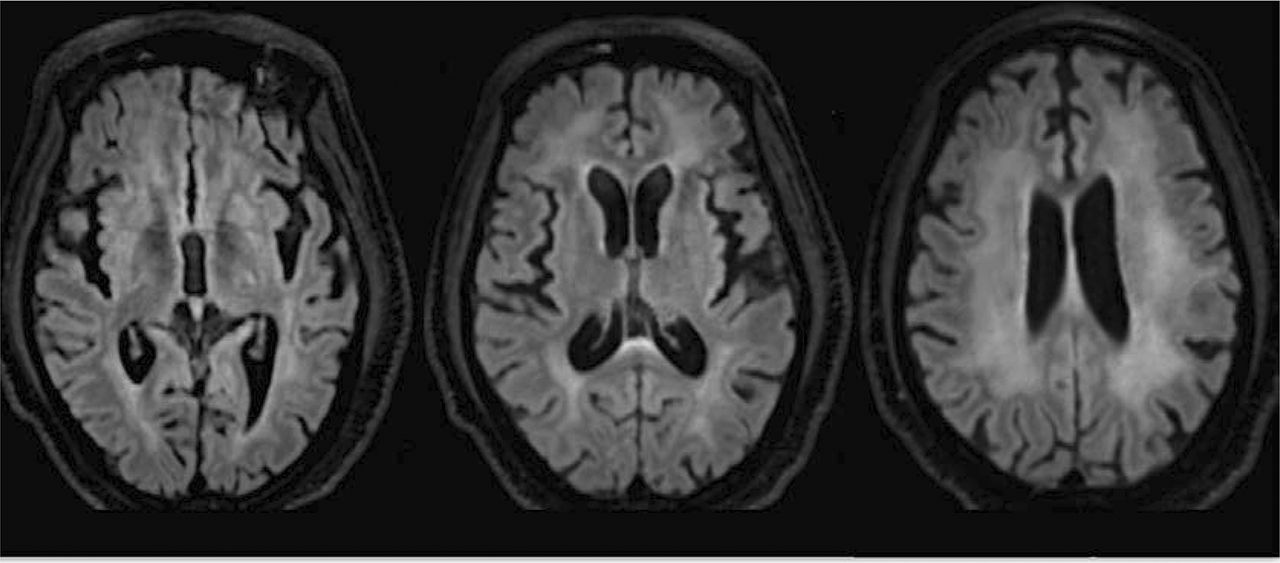

对大脑核磁共振、心室的重要性和沟与广泛对称的可视化,室周的T2 hyperintensity fluid-attenuation反转恢复(天赋)信号在幕上的白色物质,延长到放射冠(图1)。脊柱MRI是正常,没有异常增强postcontrast成像。

病人的临床和实验室研究结果强烈点对诊断为艾滋病痴呆(了)。实验室测试和神经影像有效地排除其他代谢和传染性病因,包括弓形体病和中枢神经系统淋巴瘤,表现为多个还是孤立ring-enhancing病变,分别用积极CSF的发现。相反,病人的漫射皮层下T2 hyperintensity天赋MRI更艾滋病毒脑炎的特征。此外,尽管患者的临床情况可能类似于一组,一组是一种疾病的老年人(> 65)。这个病人而不是代表了一种先进的艾滋病和。

有多种多样的临床表现和进步。早期症状包括记忆缺陷或心智功能下降,而运动症状后,包括手灵巧度下降,dysdiadochokinesia、反射亢进。存在于一个艾滋病毒相关的神经认知障碍,包括无症状神经认知障碍和轻度神经认知障碍。这些条件严重分化的神经损伤Frascati划定的标准,代表了最高程度的功能障碍。5主要运动功能障碍出现在在区分这是有用的额叶皮质下痴呆等皮质性痴呆阿尔茨海默病,它的特点是早期的种种困难除了皮质迹象像空间意识的丧失。此外,下颌反射和鼻子反射的存在,就像在我们的病人,结合室hyperintensity MRI显示额叶释放综合征的特点是。事实上,原始反射是hiv - 1的独立预测指标serostatus,特别是对于那些有认知功能障碍。7